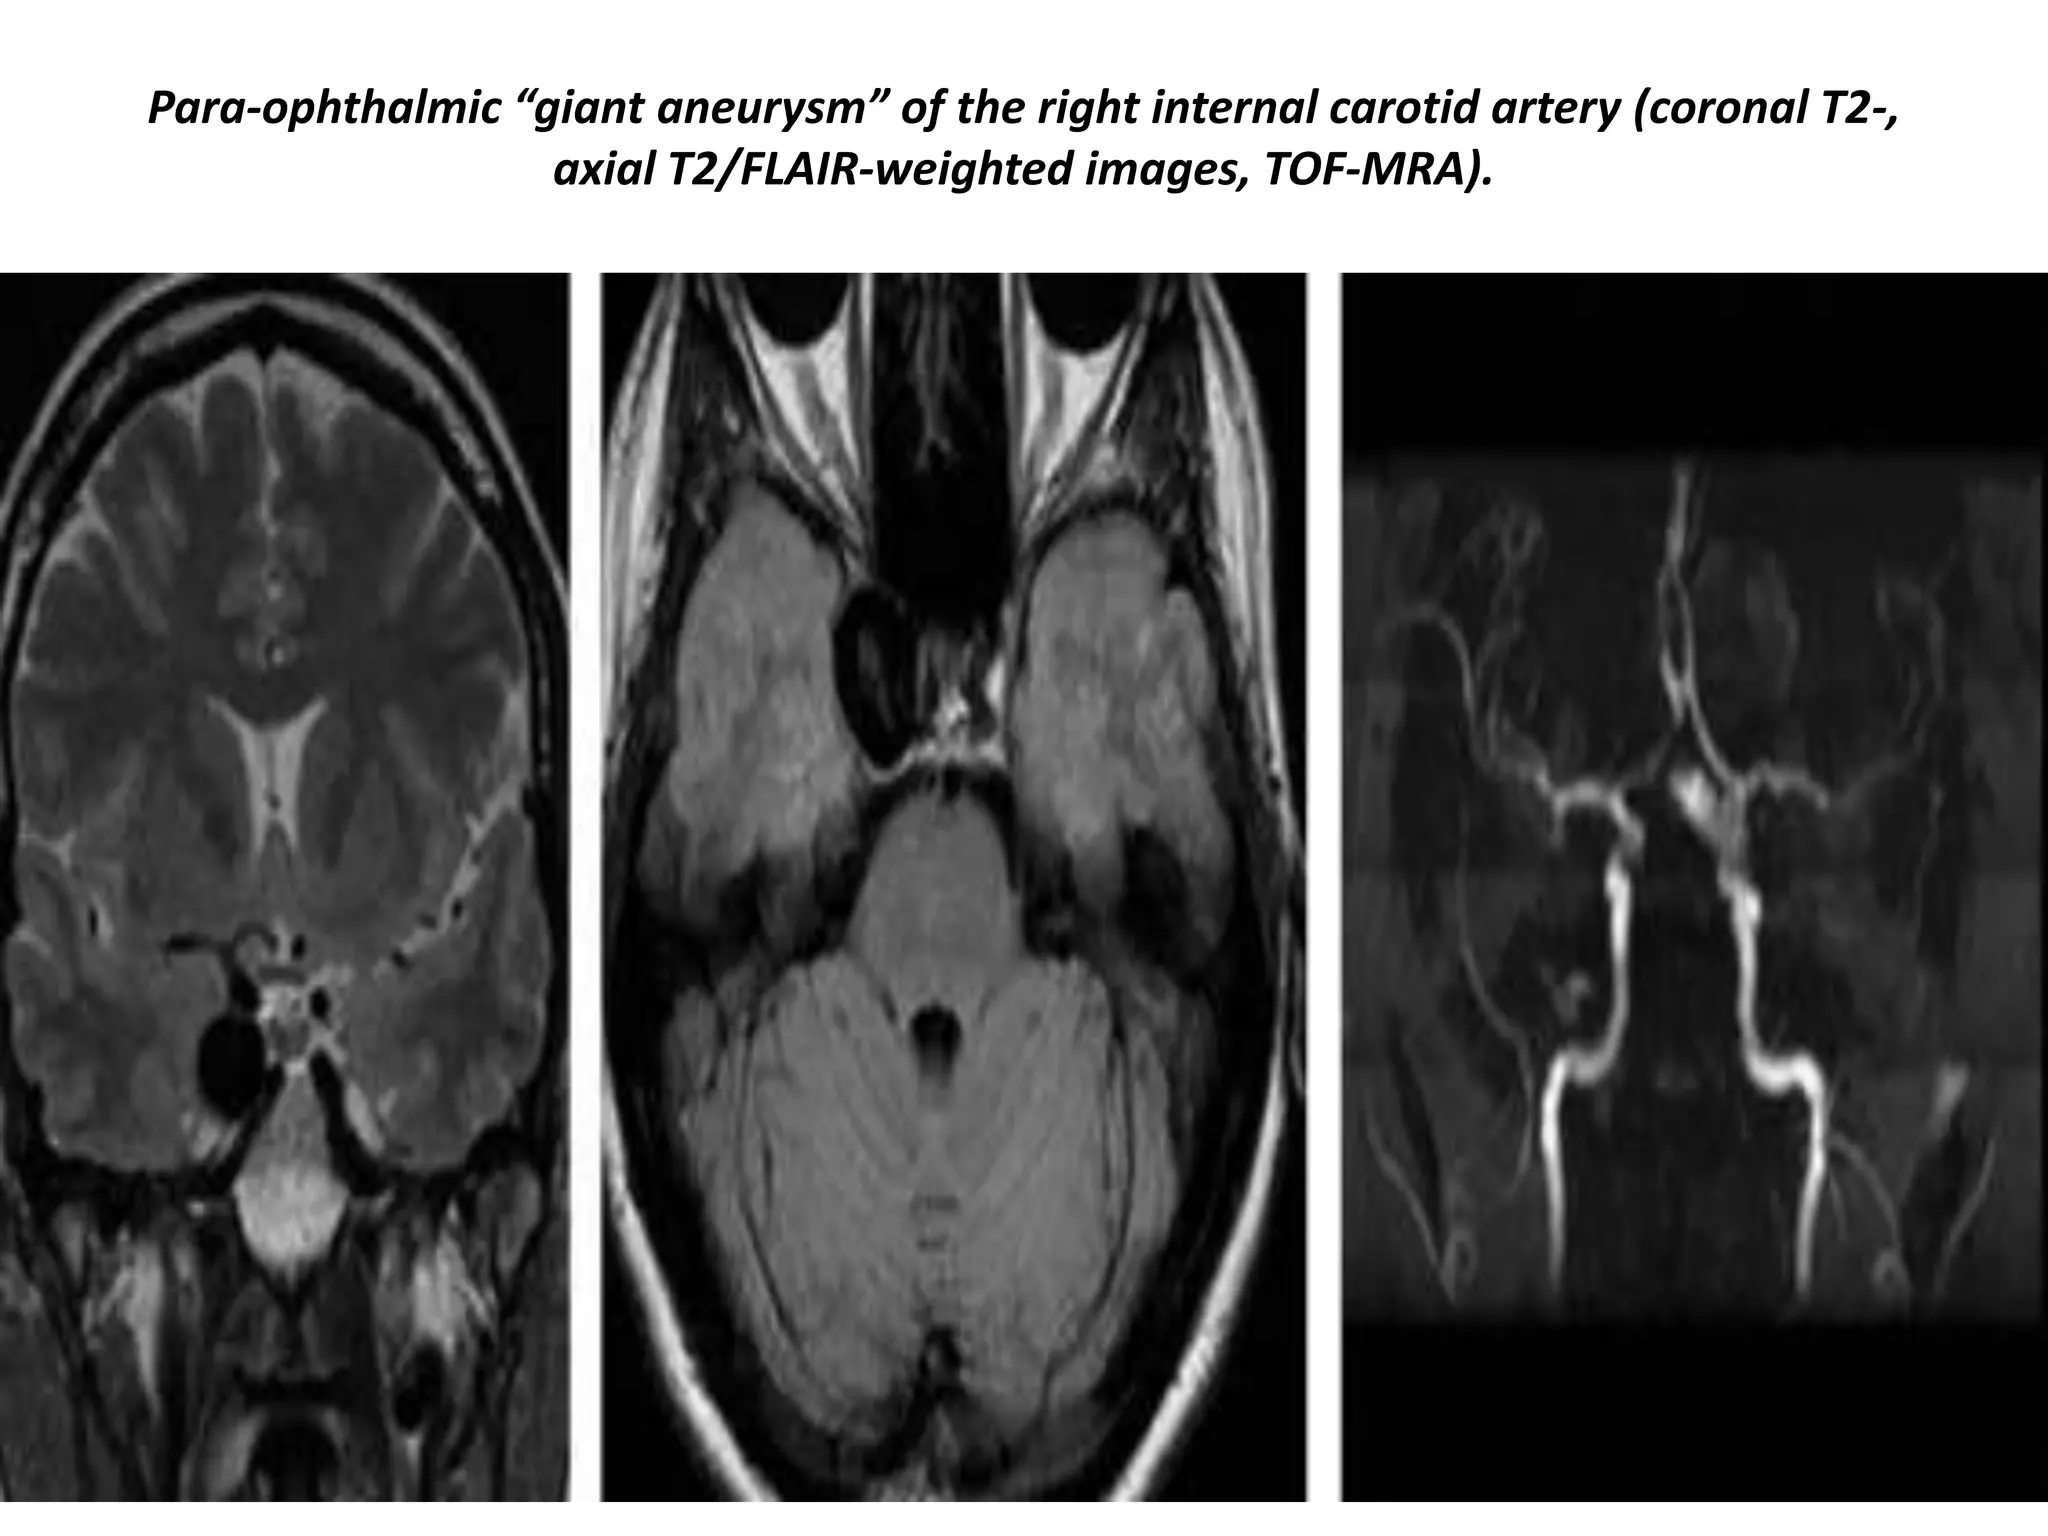

Para-ophthalmic “giant aneurysm” of the right internal carotid artery (coronal T2-,

axial T2/FLAIR-weighted images, TOF-MRA).